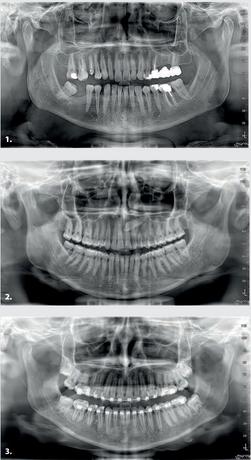

1 Orthogonal panoramic X-ray: minimises the overlapping of adjacent teeth and provides better periodontal analysis

2 Fast panoramic X-ray: low dose and reduced scan time, perfect for primary investigations, follow-ups or uncooperative patients

3 Child panoramic X-ray: limited exposure and optimised parameters for fast paediatric examinations.

4. Complete dentition divided into quadrants: localised investigations with selectable segmentation to limit the irradiated dose.

5. Bitewing projections limited to crowns: high resolution and low dose, a comfortable alternative to intraoral imaging, appreciated by patients with a strong gag reflex.

Temporomandibular joints: right and left, with open or closed mouth, and in latero-lateral and posteroanterior projections with multi-angle projection

Innovative DCIII technology, which improves depth of field and increases contrast - and therefore real resolution power - lets users obtain SuperHD panoramic images from extremely extensive datasets to provide an 11-layer MultiPAN. Highly useful in the case of complex morphologies